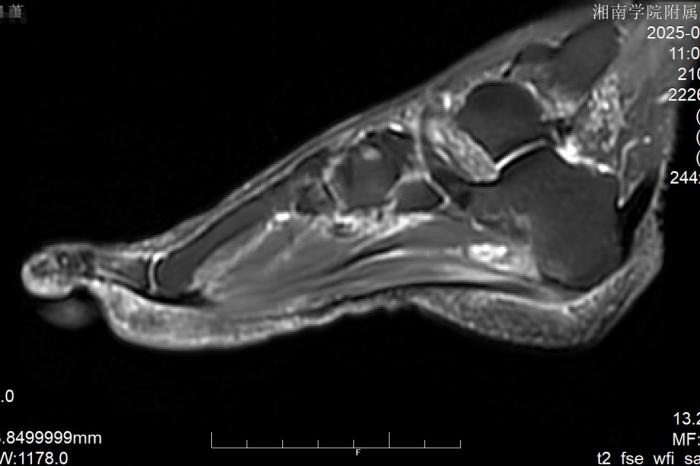

接诊后,李杨主任医师迅速带领团队为陈阿姨展开全面检查。结合患者的症状表现、病史资料以及影像学检查结果,团队明确诊断:陈阿姨患上的是足底筋膜炎,且已出现筋膜粘连与赘骨增生情况。由于病情迁延较久,传统治疗手段已难以达到理想效果,手术干预成为必要选择。考虑到陈阿姨年事已高,且希望能尽快恢复正常生活,团队经过反复研讨,最终决定采用关节镜微创技术,为其实施足底筋膜松解术与病灶清除术。